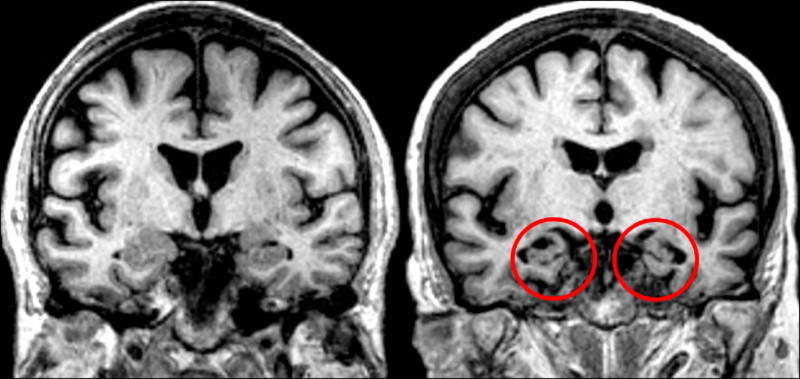

50歲謝姓男子曾是工作效率高、表現卓越的主管,不料,3年前逐漸出現記憶障礙,不僅經常忘東忘西、無法處理好交辦事項,甚至難以組織語句及表達想法,因狀態日益惡化,最後不得不離職,經哥哥陪同就醫,確診為「早發型阿茲海默症」(指65歲前發病的失智類型),因其既無家族遺傳病史,也無「三高」或慢性疾病,為家人帶來巨大衝擊。

光田綜合醫院神經內科醫師陳廷斌指出,早發型(年輕型)失智症發病原因,除了家族遺傳、腦部清除機制異常、慢性情緒障礙外,也與睡眠問題息息相關。當在深層睡眠時,大腦會啟動清除機制,將腦中的類澱粉蛋白代謝排除;若長期睡眠不足或無法進入深沉睡眠階段,這些毒素將持續堆積於大腦,損傷神經細胞,造成退化。